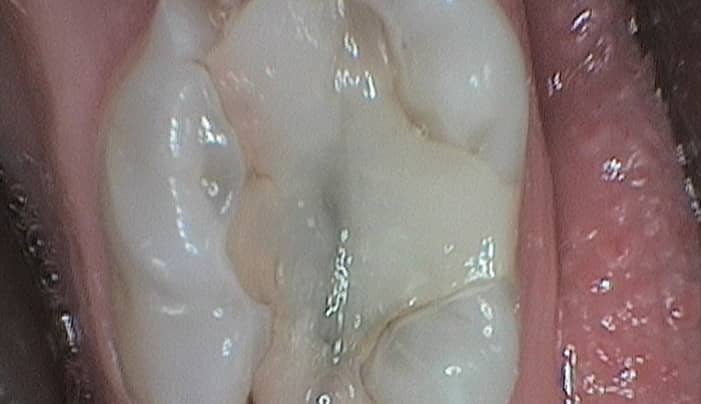

Fillings are a very simple and effective treatment used to treat a tooth that needs to be repaired or restored as a result of tooth decay. They are used to literally ‘fill’ a gap in a tooth left by a cavity.

We recommend fillings when our patients are suffering from a cavity caused by tooth decay. When left untreated they can cause toothache, an increase in sensitivity and difficulty or pain when chewing. They’ll also proceed to get larger and larger which will just lead to further and greater dental problems.

Fillings can be fitted in just one appointment. We’ll numb the area being treated so you can’t feel anything, and we’ll gently remove any decayed or weakened parts of the tooth that need to be removed. The tooth will then be cleaned and shaped and we’ll apply the filling.